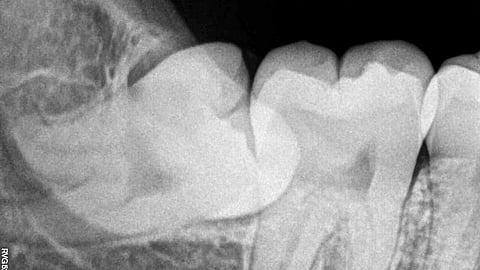

A dental X-ray showing an embedded wisdom tooth.

The tooth you threw away could have healed you: how wisdom teeth stem cells are emerging as a powerful tool.Nizil Shah, CC BY-SA 4.0, via Wikimedia Commons